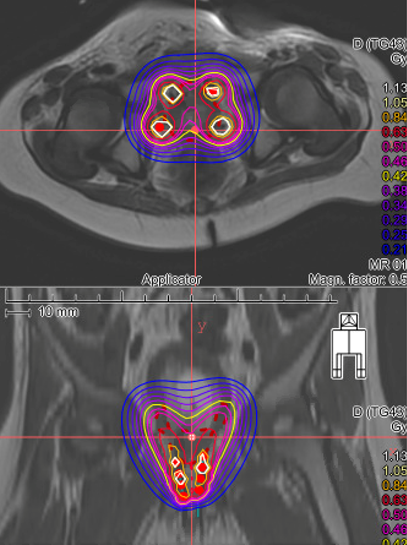

Les progrès réalisés en curiethérapie guidée par l’imagerie 3D (IRM) ces dix dernières années ont conduit les cliniciens à mieux définir les zones cibles pour la pose des cathéters et à ajuster avec précision les doses optimales à administrer.